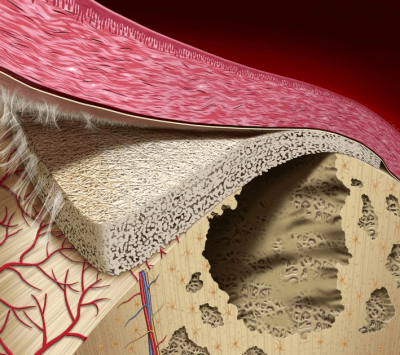

Применение костных трансплантатов в эндопротезировании тазобедренного сустава всегда было оправдано при наличии дефектов, связанных с дисплазиями вертлужной впадины, лизисом кости при ревматоидном артрите, дефектах, возникших при асептической нестабильности эндопротеза. В таких случаях применяется как структурный, так и измельченный костный материал.

Большинство ревизионных операций неизбежно требуют костную пластику либо вертлужной впадины, либо проксимального отдела бедра. До 4% бесцементных вертлужных компонентов эндопротезов требуют ревизионного вмешательства на сроках после 4 лет, что свидетельствует об отличных результатах применения бесцементной фиксации.

Применение костной пластики проксимального отдела бедра методом импакции костной стружки, а также кортикальных трансплантатов доказало свою эффективность.

Структурные аутотрансплантаты (половина головки бедра) использовались для создания необходимой формы покрытия гнезда вертлужной впадины, обеспечивающей адекватную опору. Трансплантат фиксировался одним или двумя винтами, направленными перпендикулярно линии соединения с тазовой костью.

Костные трансплантаты покрывали от 15% до 45% поверхности вертлужного компонента. Отмечалась незначительная резорбция трансплантата в 15% случаев. Оценка проводилась по методике Gerber & Harris. Ни один из трансплантатов не был фрагментирован или сломан.